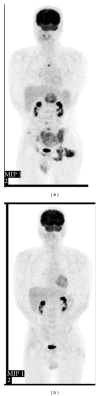

Extraskeletal mesenchymal chondrosarcoma is rare and metastasis to the pancreas is extremely rare, with only four cases reported in the literature. The therapeutic effectiveness of chemotherapy remains uncertain. We report a 39-year-old man with extraskeletal mesenchymal chondrosarcoma of the buttock, who had metastases to the pancreas, bones, and lung. He underwent distal pancreatectomy, resection of the buttock tumor, and chemotherapy. He had a good response to chemotherapy and survived for about 3 years after surgery.